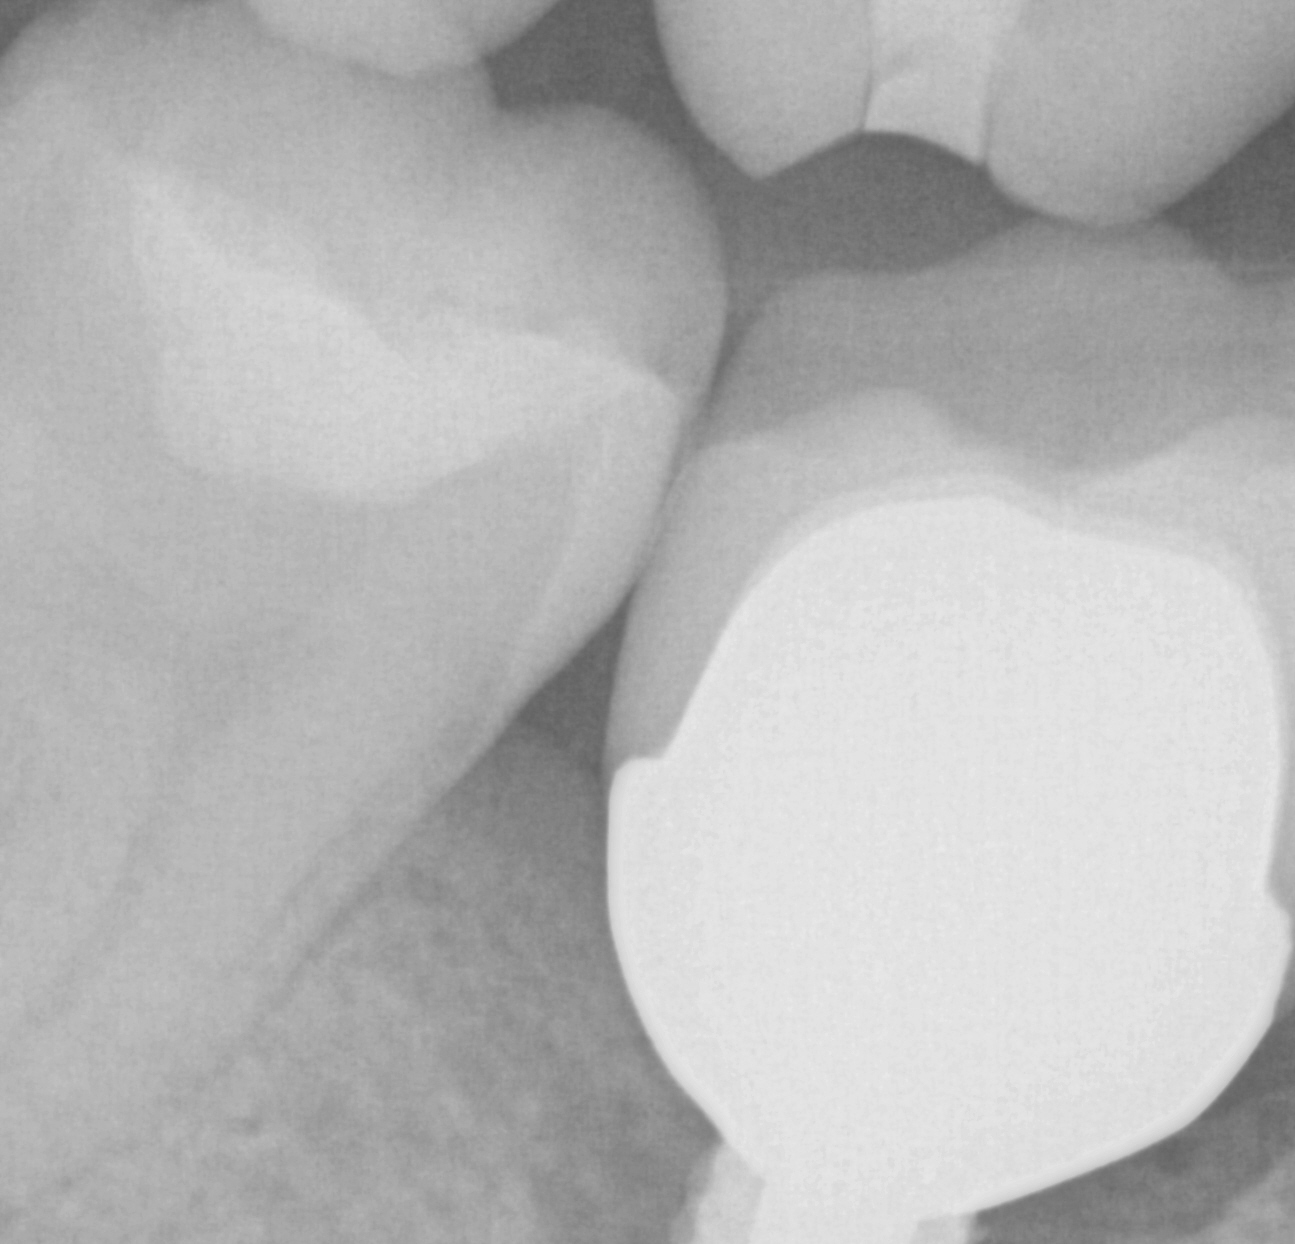

Post op x-rays to verify seat and no excess resin after flap was raised to clinically visualize that there is no excess cement